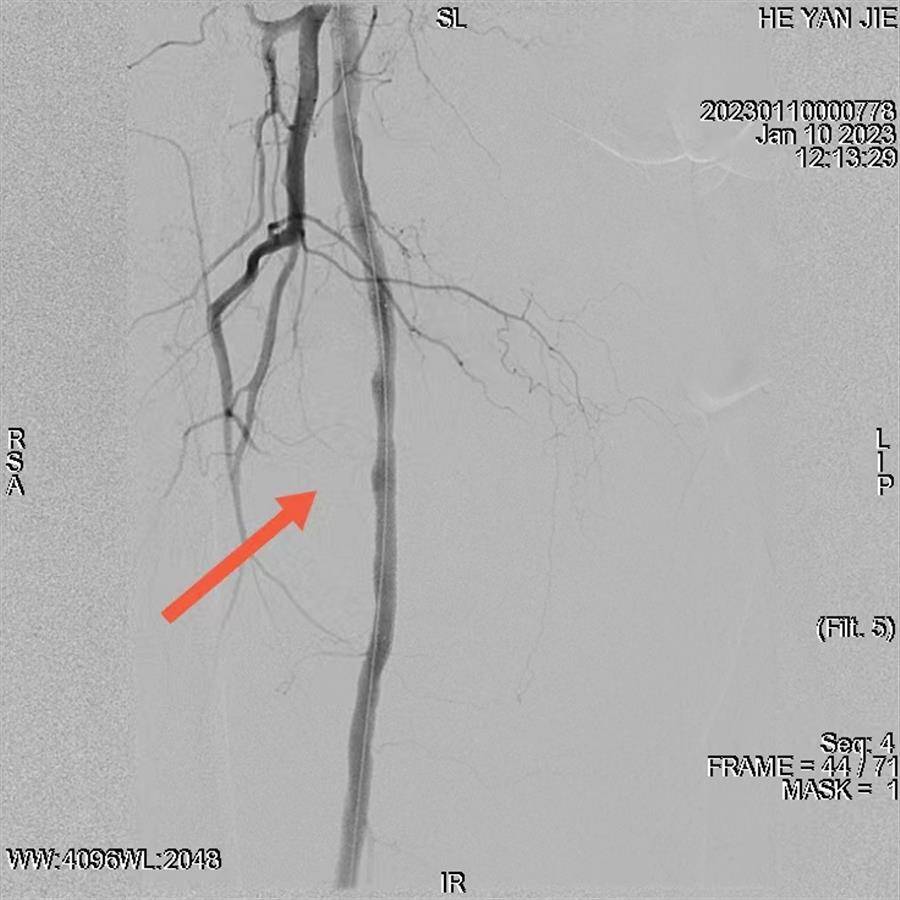

股浅动脉中段植入支架后,原假性动脉瘤瘤腔被完全隔绝,无显影

经过充分的术前准备,骨科、介入放射科、肾病内科、手术麻醉中心等多学科共同参与了手术。手术中,介入放射科副主任医师严子才发现,由于破口较大,导引导丝非常容易进入假性动脉瘤内。最后经过调整和精确修剪“开窗”,导丝和支架输送装置顺利到位,释放后完美隔绝瘤腔,成功封堵了假性动脉瘤。随后,手术麻醉中心秦智刚主任立即为患者麻醉,骨科姚士军主任主刀行微创骨折复位内固定术,期间肾病内科随时准备为患者进行透析。最终,在各方共同努力下,多学科协作的接力手术顺利完成。目前,何婆婆的术后恢复良好。